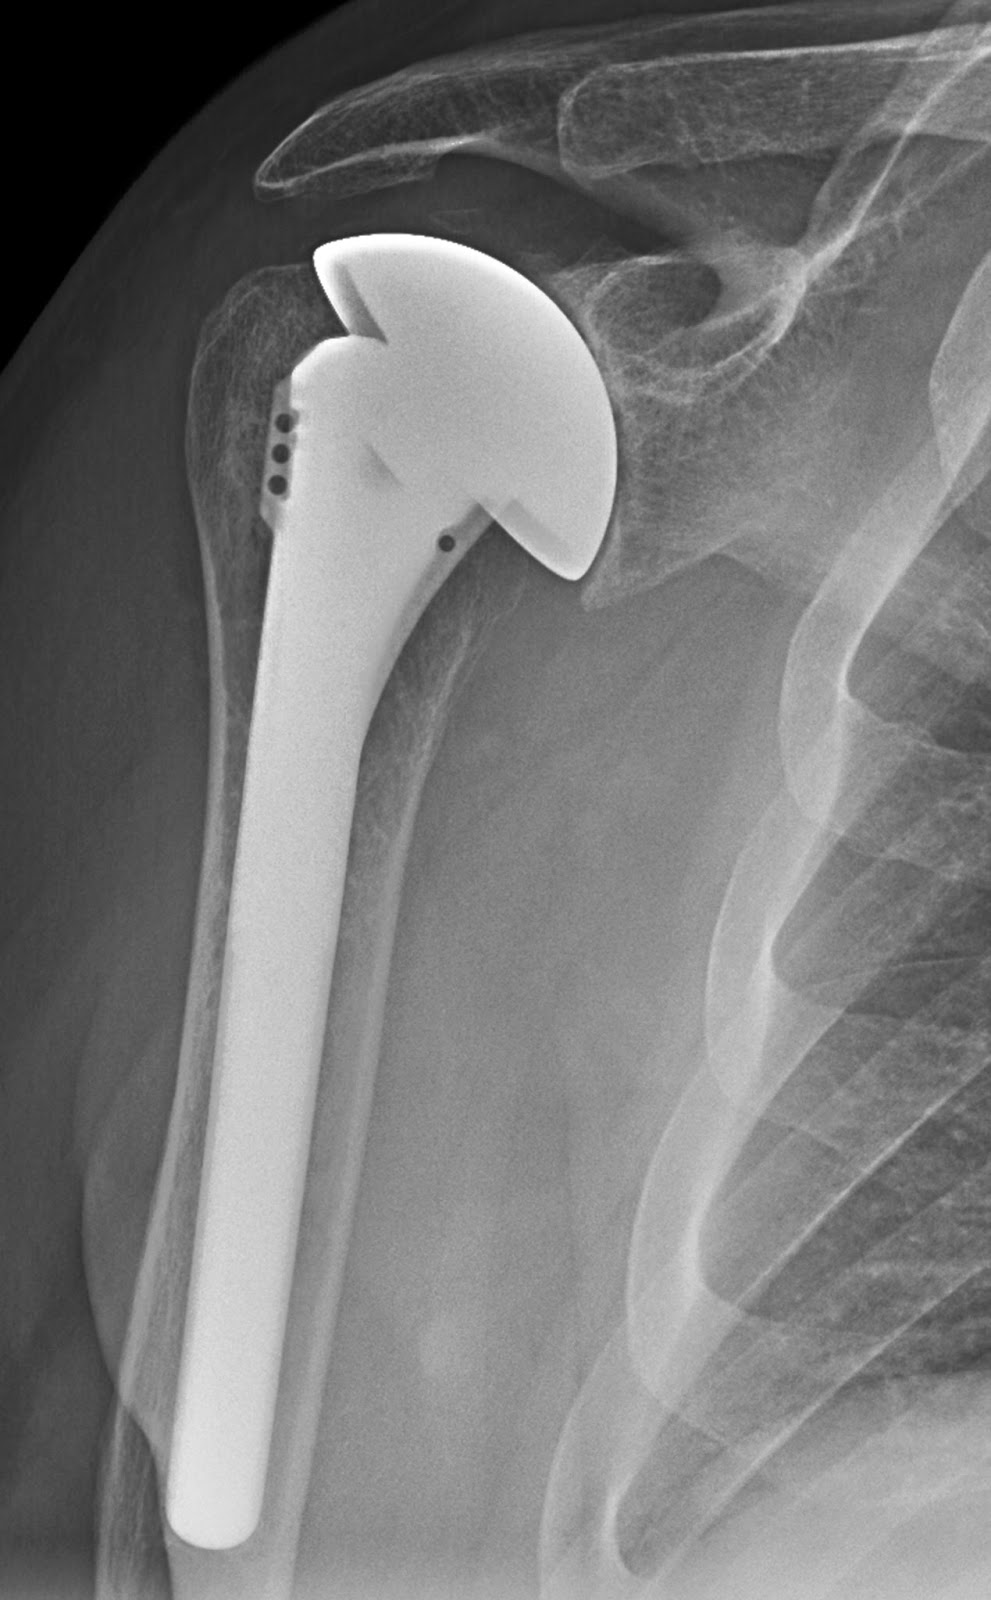

True anteroposterior shoulder plain radiograph showing the lateral What Is A Shaft Shoulder When a bearing is located against a shoulder in the mating part, care must be taken that the rim of the shoulder clears the. The shoulders of shafts or housings that support the bearing face must be perpendicular to the shaft surface or the housing bore. The assembly conditions are very important for ball bearings to function correctly. It is. What Is A Shaft Shoulder.

Neck shaft angle in reverse shoulder arthroplasty 135 vs. 145 degrees What Is A Shaft Shoulder A shaft is the component of a mechanical device that transmits rotational motion and power. Shoulder height the shoulder height (h) of the shaft and housing must be larger than the minimum allowable chamfer dimension of the bearing, and it should be a height that firmly. When a bearing is located against a shoulder in the mating part, care must. What Is A Shaft Shoulder.

UW Shoulder and Elbow Academy Humeral implants with variable neck What Is A Shaft Shoulder The shoulder heights for both shafts and housings for radial bearings should be sufficient to provide good support over the face of the bearings, but. The assembly conditions are very important for ball bearings to function correctly. A shaft is the component of a mechanical device that transmits rotational motion and power. Shoulder height the shoulder height (h) of the. What Is A Shaft Shoulder.

UW Shoulder and Elbow Academy How important is the humeral headshaft What Is A Shaft Shoulder It is integral to any mechanical system in which power is transmitted from a. A shaft is the component of a mechanical device that transmits rotational motion and power. The shoulder heights for both shafts and housings for radial bearings should be sufficient to provide good support over the face of the bearings, but. Shoulder height the shoulder height (h). What Is A Shaft Shoulder.